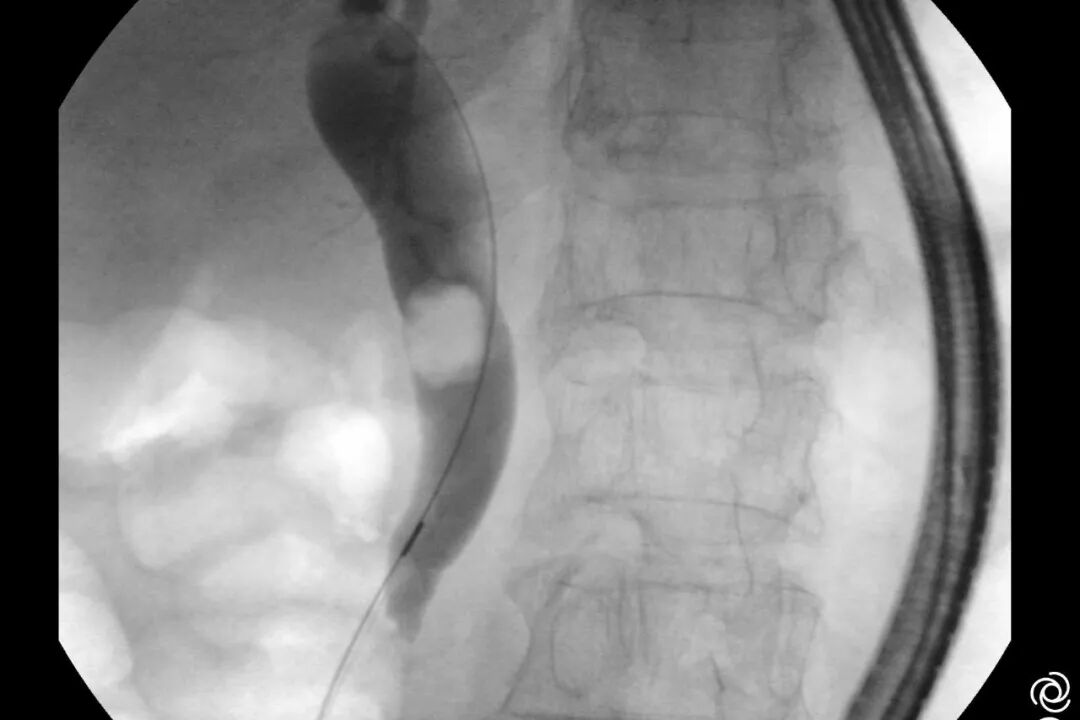

图片

术中-胆管造影

术中胃镜戴透明粘膜吸套进镜,可见胃、十二指肠、空肠呈B-II式术后改变,吻合口发红。经团队仔细查找,于输入袢找到十二指肠大乳头,插入三腔括约肌切开刀,并顺利将导丝送入胆总管。造影验证,可见胆总管明显扩张,直径最宽处约16mm,中段见一长条形结石影,约13x12mm。切开乳头后,扩张乳头括约肌及胆总管括约肌,用特制取石导管及取石网篮取出大量黄色块状结石及碎渣样结石。术后置入鼻胆引流管引流,顺利结束手术